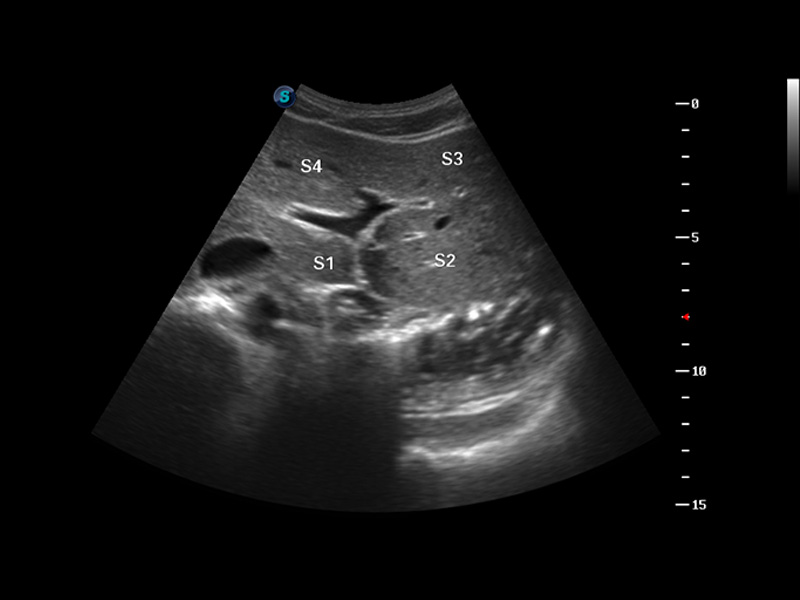

S8 EXP便攜式彩色多普勒超聲診斷儀是開(kāi)立醫(yī)療研發(fā)的高端全身應(yīng)用型便攜彩超。高通道的VIS平臺(tái)融合可視化(Visual)、智能化(Intelligent)和人性化(Smart)的特點(diǎn),配以開(kāi)立醫(yī)療自主研發(fā)生產(chǎn)的探頭大家族,使您能夠快速、準(zhǔn)確的獲得病人信息,提高工作效率的同時(shí)減輕疲勞。

成像技術(shù)

μ-Scan微米成像

諧波成像